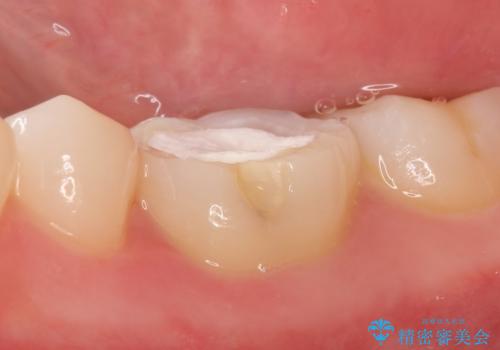

顕微鏡下で精密根管治療を行い、症状の緩解を確認後、オールセラミッククラウンによる補綴を行いました。

今回用いたオールセラミッククラウンはジルコニアフレームという白い素材の上にセラミックを盛っているため、審美性が非常に高いのが特徴です。

また、ジルコニアは人工ダイヤモンドの材料にも使われているほど高い強度を持っており、そのためオールセラミッククラウンは審美性だけでなく、奥歯やブリッジの補綴も可能とするクラウンです。